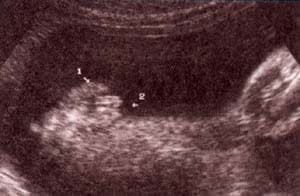

fig. 49.– (a). genitales externos xx. labios mayores (1) . 32 semanas. fig. 49. – (b). labios menores fusionados (2). 32 semanas.